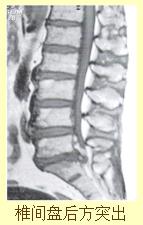

腰间盘突出

据统计约50%的病人表现为先腰背痛后腿痛,约33%的病人为腰背痛和腿痛同时出现。约17%先腿痛,后腰背痛,95%的病人椎间盘突出部位在L4-5和L5-S1,椎间隙,故病人多有坐骨神经痛,疼痛部位由腰胯部、臀后部、大腿后外侧,小腿外侧至根部或足背部,后期病人常表现坐骨神经痛重于腰背痛或仅有坐骨神经痛,严重者下肢瘫痪。